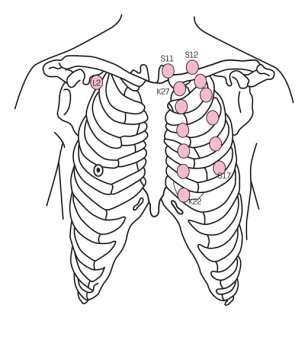

Figuur 2 | Acupunctuurpunten waarbij het risico op beschadiging van de longen verhoogd is, zijn gerelateerd aan de maag (S11-17), de nier (K22-27) en de long (L2)5

Acupunctuurpunten waarbij het risico op beschadiging van de longen verhoogd is, zijn gerelateerd aan de maag (S11-17), de nier (K22-27) en de long (L2)

Over het algemeen beschouwt men acupunctuur als veilig, maar tijdens en na de behandeling kunnen complicaties optreden. Er zijn veel verschillende complicaties beschreven, waaronder orgaan- en weefselschade (pneumothorax, zenuwschade), infecties (hepatitis, tetanus), lokale complicaties (contactdermatitis, allergische reacties) en systemische complicaties (duizeligheid, syncope).67 Uit prospectieve onderzoeken is gebleken dat milde complicaties, zoals een lokale bloeding, optreden bij 6,7 tot 15% van de patiënten die acupunctuur ondergaan.812 Ernstige complicaties, waarvan pneumothorax de meest voorkomende is, treden zeer zelden op.1315 Een recent Taiwanees onderzoek geeft als incidentiecijfer voor pneumothorax na acupunctuur 1,75 per miljoen patiënten als de acupunctuur plaatsvindt in een risicogebied van het lichaam. Risicogebieden zijn schouders, thorax en bovenrug [figuur 2], niet-risicogebieden zijn de extremiteiten en de onderrug.16 Dat acupunctuur in de genoemde risicogebieden de kans vergroot op het ontstaan van een pneumothorax wordt bevestigd door meerdere case reports.31719 Ook bij onze patiënte werd de pneumothorax veroorzaakt door acupunctuur van rug en schouders.